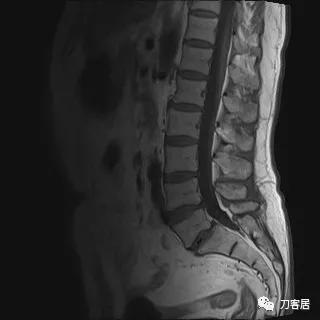

入院后予以腰椎CT及MRI检查,未见明显之椎间盘突出及椎管狭窄。

图11. 20210626术前腰椎MRIT2相1

图12. 20210626术前腰椎MRIT2相2